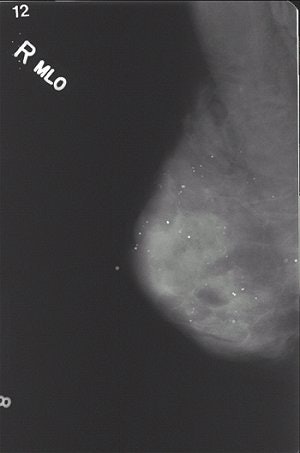

| FSM (above) and FFDM (below) scans from a 47-year-old woman with dense breasts. Images courtesy of Edward Hendrick, Ph.D., department of radiology, Feinberg School of Medicine, Northwestern University, Chicago. |